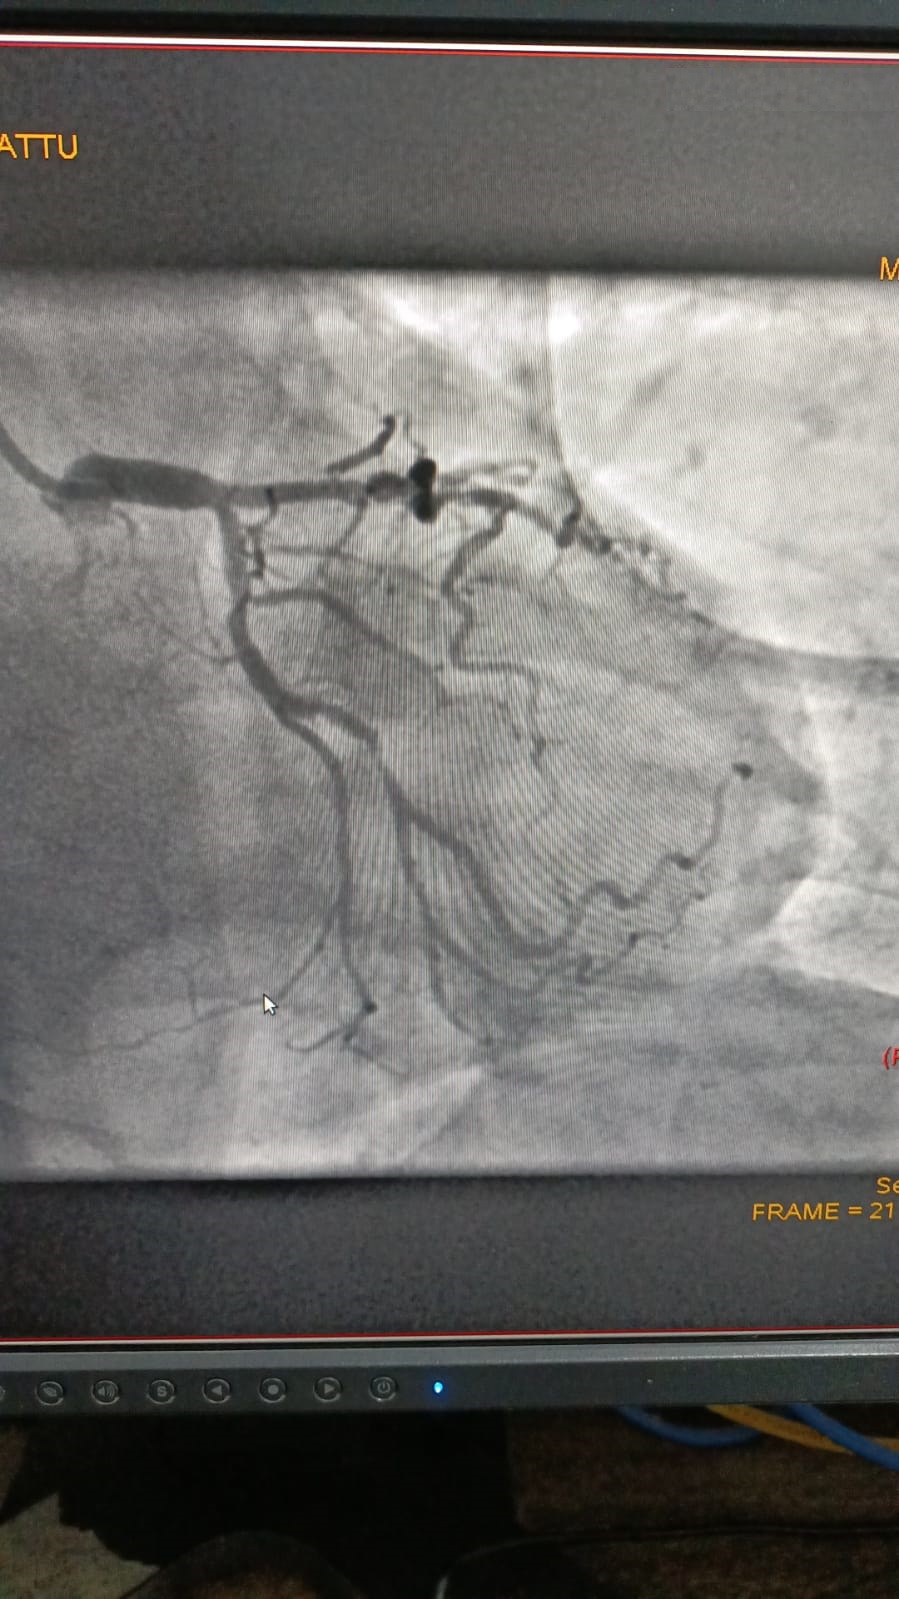

Left Coronary Artery